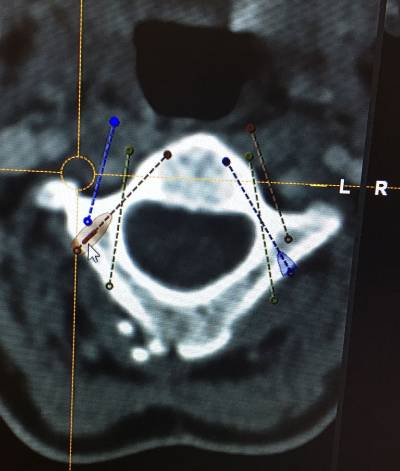

Atlantoaxial Instability Treatment 2Atlantoaxial Instability Treatment 2After the preoperative analysis of the Magnetic Resonance Imaging (MRI) and CT scan of each patient, we perform a thin sliced preoperative CT oriented towards neuronavigation that will be carried out during surgery. Prior to surgery we perform a surgical planning of the intraoperative neuronavigation to confirm the trajectories of screws and special anatomical dispositions of structures. It is also important to know and evaluate patients’ concomitant diseases or comorbidities which are frequent in patients affected by Ehler Danlos, such as POTS, Mast Activation Syndrome, cardiac abnormalities … etc. Knowing this it allows to anticipate any possible problems in the postoperative period.

Once in the Operating Room, surgery is performed under general anesthesia, with Neurophysiological monitoring (SSEP – somatosensory evoked potentials), neuronavigation guidance and intraoperative fluoroscopy guidance. Thus we control the spinal cord and nerves (cranial and cervical) in order to avoid potential damages to these important structures. Neuronavigation assistance guides us all through the surgery, thus it diminishes (though it does not eliminate) the risks while placing the screws for the fusion. Both neurophysiological monitoring and neuronavigation guidance are safety measures for the patient.